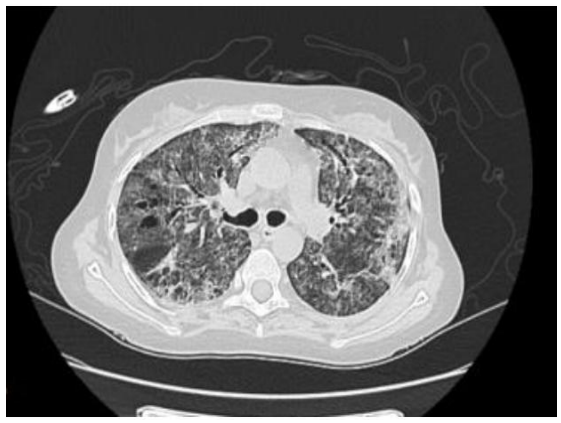

The evolution was marked by the onset of acute febrile dyspnea with desaturation at 50, requiring intubation. Biology showed 350 elements/ mL lymphopenia with a positive CMV PCR: 86982 IU/ mL. Chest CT (Image 2) showed diffuse reticular-micronodular opacity with a positive search for pneumocystis jiroveci. A search for pneumocystis jiroveci was positive. The patient was put on ganciclovir and broad-spectrum antibiotics based on cephalosporines (ceftriaxone), quinolones (levofloxacin), and immunoglobulin (tegelin). She passed away within 24 hours following a state of septic shock.

Image 2: Patient’s thoracic CT scan